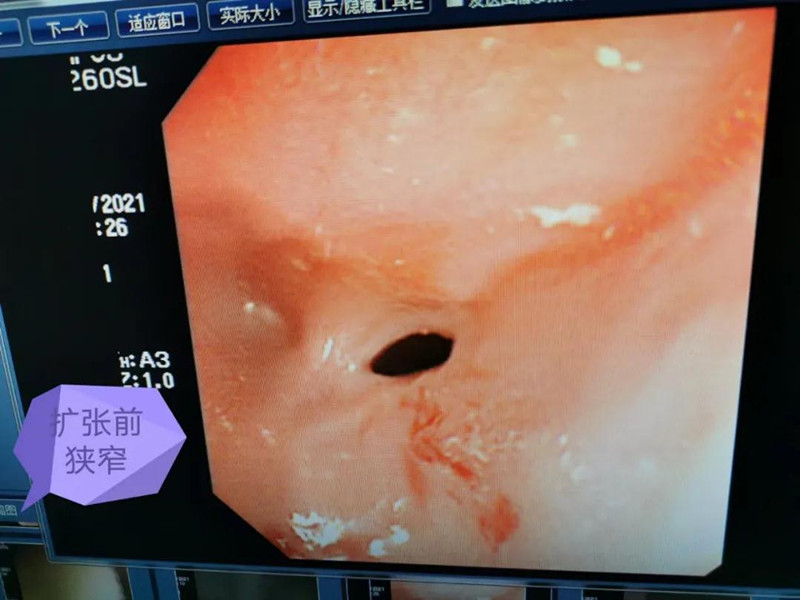

天天6个月了。最近总出现呛奶的情况,后来还出现肺炎症状。在蜜桃视频 经食道造影后,医生发现天天的症状是由术后并发症“食道吻合口狭窄”引起的,最窄处仅5mm多一点。食道狭窄球囊扩张术是目前最适合天天的手术了。内镜中心副主任边鹏说,这是一种微创介入治疗,具有创伤小、恢复快、合并症少的优势。2月26日,在麻醉科、内镜中心团队的合作下,边鹏为天天行经内镜下食道狭窄球囊扩张术。术中,边鹏用直径8mm的球囊进行扩张,将原来狭窄的食道扩成直径8mm的宽度。

天天太小,在球囊扩张的过程中,需要格外注意,不能扩张太快,否则会出现穿孔或大出血。所以边鹏每扩张3分钟,暂停3分钟,共扩张了3次。整个扩张过程很顺利,效果也非常好。次日,天天就出院了。在球囊扩张前,小儿内镜下显示,天天食道吻合口狭窄处上端竟有一团纸,家长也不清楚孩子是什么时候吃了纸。因为吻合口处太窄,纸下不去,形成了阻隔,导致天天最近总呛奶,奶汁进入气道,最终出现肺炎。